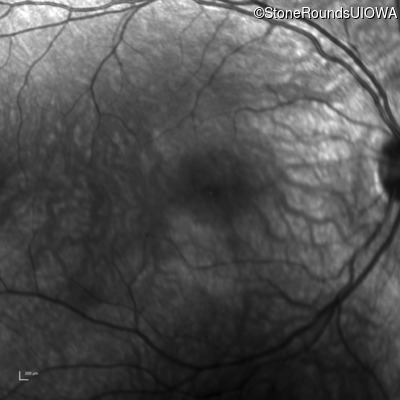

Infrared Fundus Photograph - Left - 10/200

Exemplar